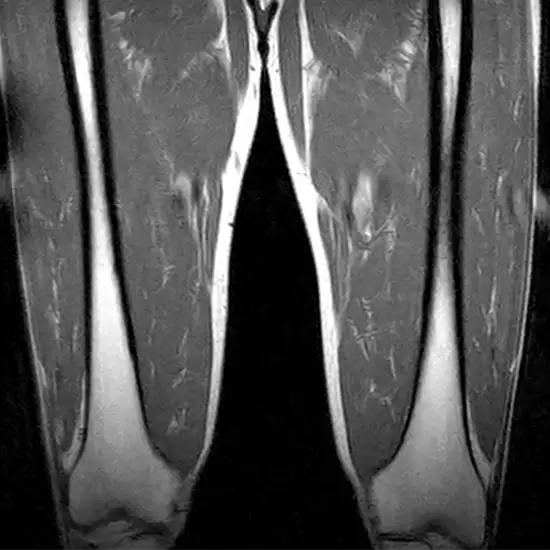

An MRI scan of the thigh is used to visualize the thigh bone and the soft tissues around it, such as cartilage, tendons, ligaments, muscles, and blood vessels.

An MRI of the thigh is performed to determine the origin of leg discomfort and thigh bone fractures. This examination reveals abnormal development in the thigh muscles or surrounding soft tissues.